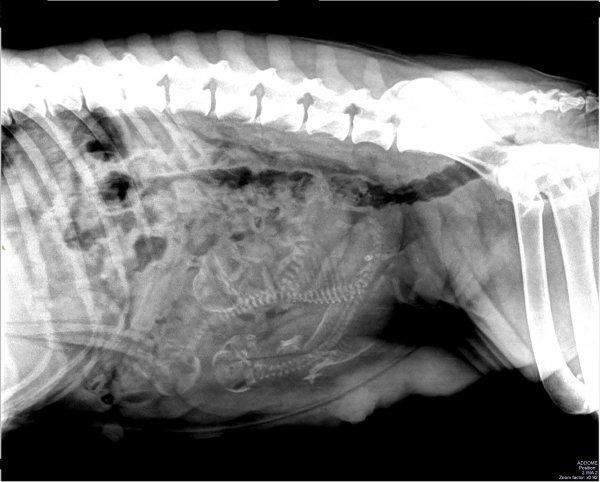

Cause anche l’alimentazione, le allergie alimentari, l’ingestione di prodotti chimici o corpi estranei, parassiti interni, infezioni batteriche o virali, possibili neoplasie. Alcuni dei sintomi clinici di gastrite nel cane e nel gatto sono vomito e dolore addominale,consequente disidratazione, inappetenza e perdita di peso, diarrea e sangue nelle feci.

La visita gastroenterologica comprende,

Visita e indagini diagnostiche in base all’anamnesi e ai sintomi del paziente Analisi di laboratorio(esami delle feci per la ricerca di parassitosi

intestinali)

Esami del sangue per valutare funzionalità pancreatica ed epatica Radiografia addominale /radiografia toracica Ecografia addominale Endoscopia - gastroduodenoscopia